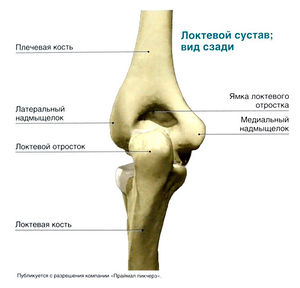

Задняя поверхность

- Локтевой отросток

- Подкожная локтевая сумка

- Трехглавая мышца плеча